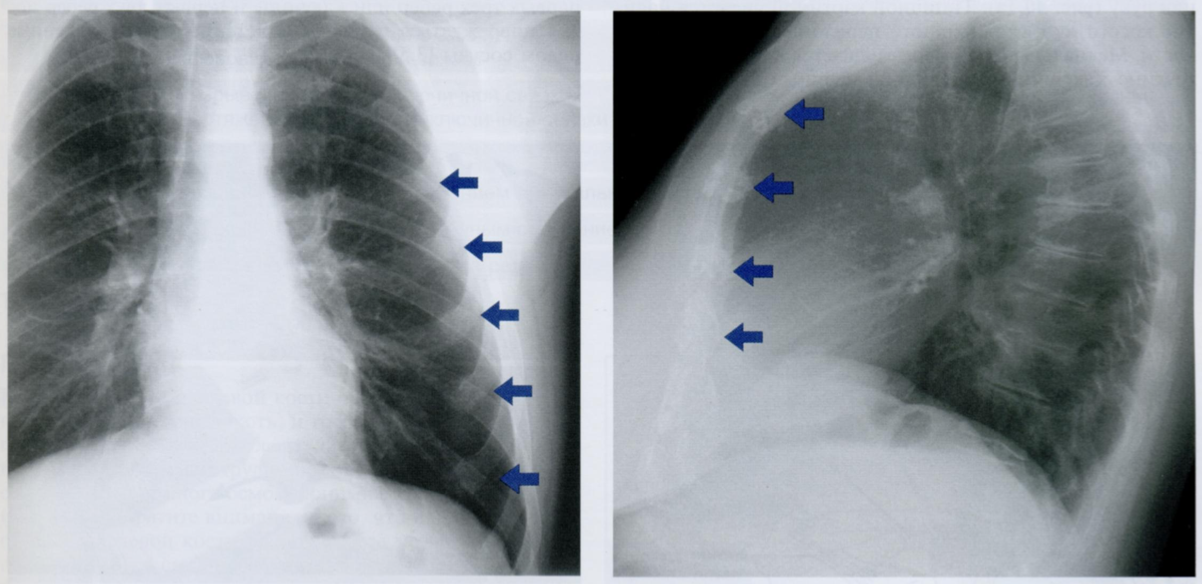

Как Вы оцените объекты отмеченные на снимке, принимая во внимание, что клиника и снимок никак нет коррелируют?

ЗПП - задняя прямая проекция и БП - боковая проекция

То есть, вероятнее всего, это артефакты. Какие?

Стрелками на первом снимке отмечены заплетенные и распущенные волосы, которые приводят к появлению артефатков, которые имитируют восходящий пневмомедиастинум или подкожную эмфизему.

На втором снимке мы видим ампутационную культю руки в БП, которая выглядит как веслообразное затемнение на уровне проекции верхнего средостения. Может имитировать новообразование.